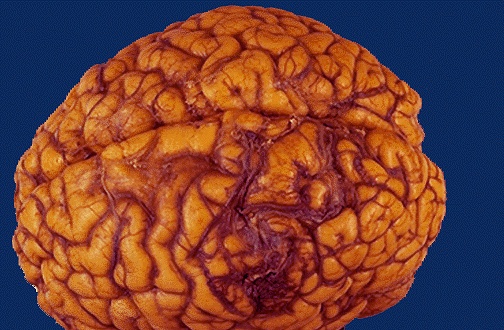

Another cause for hemorrhage, particularly in persons aged 10 to 30, is a vascular malformation. Seen here is a mass of irregular, tortuous vessels over the left posterior parietal region. [Image contributed by Jeannette J. Townsend, MD, University of Utah] |